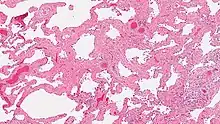

A photomicrograph of SRIF as seen by a pathologist through a microscope. The tissue on the slide is stained with two standard dyes (hematoxylin: blue, eosin: pink) to make it visible. . Note that the excess collagen in SRIF gives the air sacs a pink color.

Smoking-related interstitial fibrosis (SRIF) is an abnormality in the lungs characterized by excessive collagen deposition within the walls of the air sacs (interstitial fibrosis). This abnormality can be seen with a microscope and diagnosed by pathologists. It is caused by cigarette smoking.[1][2]

The defining feature of smoking-related interstitial fibrosis is a distinctive/unique type of fibrosis characterized by "ropey" collagen bundles within the walls of the air sacs (alveoli), almost always in association with other smoking-related abnormalities such as pigmented macrophages and emphysema.[6]